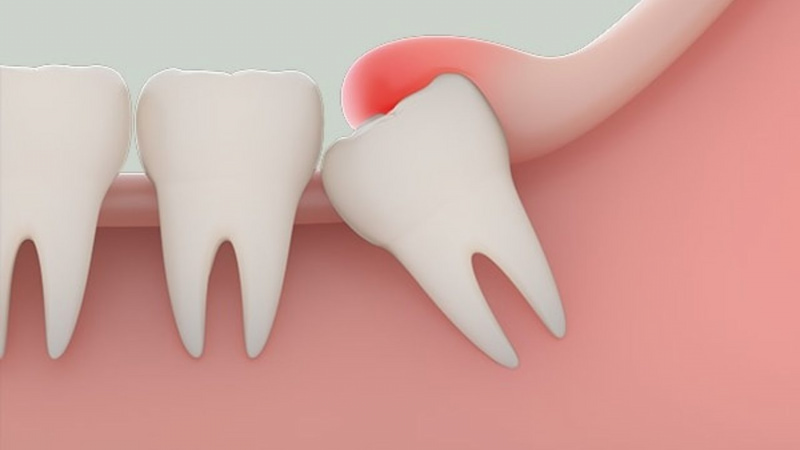

- Mức độ phức tạp của răng: Răng mọc thẳng, dễ tiếp cận sẽ có chi phí thấp hơn so với răng mọc lệch, mọc ngầm, nằm ngang hoặc gần dây thần kinh, đòi hỏi kỹ thuật và thời gian xử lý cao hơn.

- Tình trạng bệnh lý kèm theo: Răng bị viêm lợi trùm, nhiễm trùng, có mủ hoặc tổn thương lan sang răng bên cạnh cần xử lý trước, làm tăng tổng chi phí điều trị.